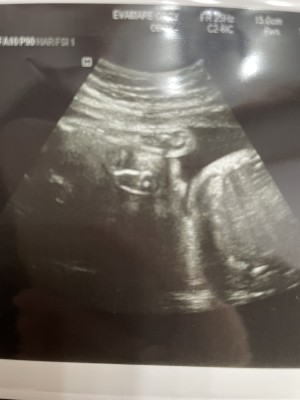

내사랑 율

듬직한 울아들 율 ? 그동안 딸인줄알았는데 존재감확실한 아들이였네 ??? 무럭무럭 건강하게 잘크고있다고해서 너무좋다 엄마가 태어날때까지 뱃속에서 잘지켜줄게? 나오면 아빠랑같이 더잘지켜줄게 따랑해 내애기